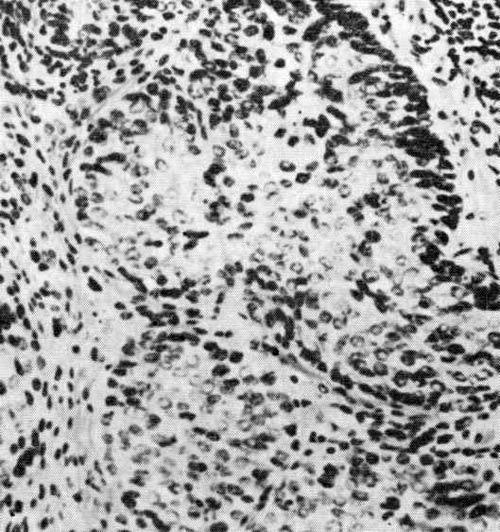

Гистологически карциноидные опухоли толстой кишки могут характеризоваться «розеткой», или псевдожелезистым строением (тип С), или солидными гнездами, иногда с десмоплазией, образованием трабекул (тип А). Возможно смешение типов А и С. Карциноиды прямой кишки могут представлять собой тип А с десмоплазией, а также тип В в виде узких лент. Карциноидные опухоли, имеющие строение, соответствующее одному из классических …